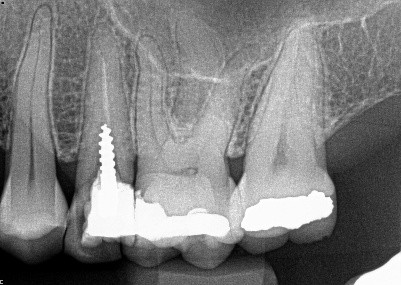

1.  (Select ONE OR MORE correct answers)

What observation(s) can be made for tooth 3.4?